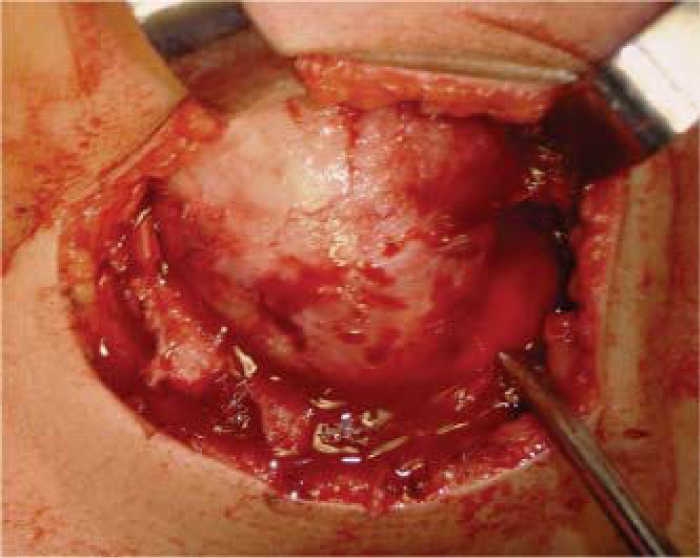

Six year old female patient exhibiting volume increase at the right side of the mandible. Lesion was of a four month evolution. Lesion was of rapid growth and elicited mild pain (Figure 1). Intraorally, expansion of mandibular cortical bone at molar level could be observed. Three-D tomogram confirmed widespread bone destruction (Figure 2). Patient's general health had not been compromised with absence of general signs and symptoms. Laboratory results were within normal parameters. Incisional biopsy report revealed benign mandibular osteoblastoma. In view of lesion's widespread destruction and aggressive local behavior, a right hemi-mandibulectomy was performed (Figure 3). A mandibular reconstruction prosthesis with condyle was placed on the surgical bed (Figure 4). Post operative control showed suitable oral opening, with undamaged main nerve structures, motor and sensory nerves preserved their continuity (Figure 5).